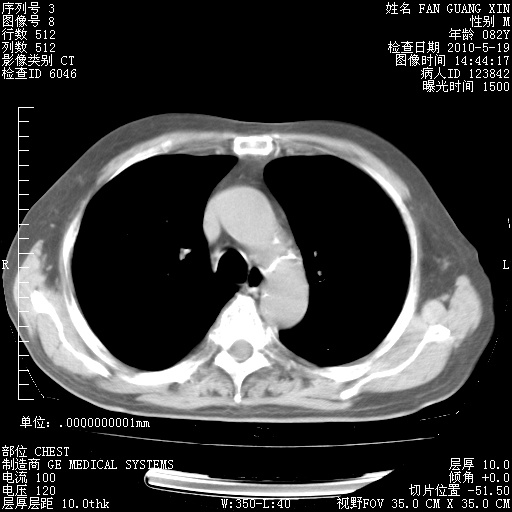

可改为口服强的松40-50mg/d治疗,若病情仍稳定,胸部阴影不再吸收可逐渐减量